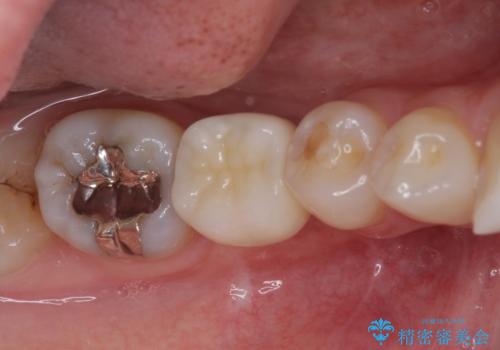

[歯の破折] インプラント埋入を行うための大規模骨造成

![[歯の破折] インプラント埋入を行うための大規模骨造成の症例 治療前](https://seimitsushinbi.jp/wp/wp-content/uploads/2020/11/073ce5e06775df372887a513b05b34d0-500x350.jpg?v=1606392481)